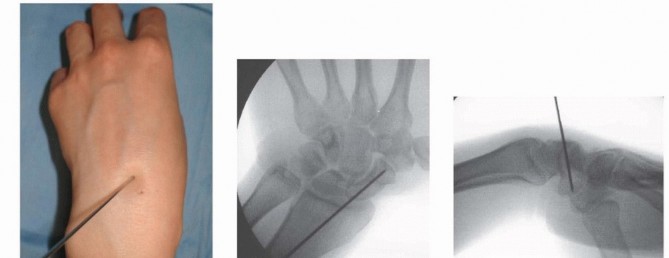

1. ## Volar Percutaneous Approach Position the patient in a supine position with the shoulder abducted and the forearm in supination. The wrist is placed into an extended and ulnarly deviated position over a rolled towel to gain access to the distal pole of the scaphoid. 12 Position the portable fluoroscopy unit such that PA and lateral views of the wrist can be obtained. Image intensification is used to locate the distal scaphoid tuberosity. A small longitudinal stab incision is made at this point, and the soft tissues are bluntly dissected down to the scaphotrapezial articulation. Introduce the guidewire on the distal scaphoid tuberosity. Under image guidance, the wire is advanced toward the center of the proximal pole, aiming for the Lister's tubercle ( TECH FIG 4). The volar prominence of the trapezium may be partially excised to facilitate the correct starting point and trajectory for the guidewire.

*TECH FIG 4 • A-C. In the percutaneous volar approach, the guidewire is inserted into the scaphoid at the scaphotrapezial joint and into the center of the proximal pole. The wire should be inserted aiming for the Lister's tubercle. Alternatively, the guidewire may be placed directly through the trapezium into the scaphoid distal pole. 11 Advance the guidewire to the subchondral bone of the proximal pole. Place a second guidewire of equal length against the surface of the distal scaphoid, adjacent and parallel to the first guidewire. The difference between the lengths of the wires represents the length of the scaphoid. Subtract 4 mm from the length of the scaphoid to obtain the desired screw length. Use the cannulated reamer to ream the near cortex. Insert an Acutrak 2 or mini-Acutrak 2 screw (or a screw from the surgeon's chosen system) of appropriate length, remove the guidewire, and confirm satisfactory screw position and fracture reduction with fluoroscopy. 117 ## PEARLS AND PITFALLS Dorsal Technique Injury to dorsal 1. Blunt dissection through the capsule minimizes the risk of injury. structures Malpositioning of guidewire 1. Pronate and flex the wrist until the ring sign is noted; the center of the ring is the insertion point for the guidewire. Screw penetration 1. Select a screw that is at least 4 mm shorter than the measured length of the scaphoid. 2. A common mistake is to place a screw that ends up too long once the screw compresses the fragments. 3. Confirm central position of guidewire via fluoroscopy. Reduction of unstable fracture 2. Kirschner wires may be used as joysticks for reduction. 3. A derotational Kirschner wire should be placed before reaming and screw insertion if the fragments are unstable. Extremely small proximal pole fractures 1. Use a mini-Acutrak 2 screw to prevent comminution of the proximal fracture fragment. Volar Technique Injury to volar structures 1. Blunt dissection to the scaphoid minimizes the risk of injury. Malpositioning of guidewire 4. A central starting point on the distal scaphoid tuberosity can be hindered by the trapezium. 5. Part of the volar trapezium can be resected to achieve a correct starting point for trajectory of the guidewire, or the wire may be inserted through the trapezium. Screw penetration 1. Select a screw that is at least 4 mm shorter than the measured length of the scaphoid. 2. Confirm central position of guidewire via fluoroscopy. ## POSTOPERATIVE CARE Dressings are applied, and the limb is immobilized in a forearmbased splint, immobilizing only the wrist. The thumb and fingers remain free for range-of-motion exercises. The patient is instructed in the importance of limb elevation and finger range-of-motion exercises. At 2 weeks postoperatively, the sutures are removed, a removable wrist splint is applied, and a wrist range-of-motion exercise program is initiated if fixation is rigid, the fracture is stable, and bone quality is good. If the patient is noncompliant, the fracture is deemed unstable, the fixation is less than ideal, or bone quality is poor, then a short-arm cast is applied for at least 6 weeks. Plain radiographs are obtained at 2, 6, 12, and 24 weeks postoperatively. The splint (or cast) is discontinued when union is confirmed on serial plain radiographs. If there is any question regarding fracture union, a CT scan is obtained. Unprotected strenuous activity or contact sports are not permitted until 3 months postoperatively. Contact sports may be permitted sooner in a brace depending on the type of sport, player position, and quality of fixation. ## OUTCOMES Results of contemporary techniques of percutaneous fixation are excellent; it has been shown to allow for earlier mobilization and return to activity and high satisfaction rates compared to nonoperative measures. 3, 5 , 11, 12, 23, 24, 32 The surgical approach (dorsal vs. volar percutaneous) does not affect the clinical and functional outcome. 11 Use of the transtrapezial approach does not lead to symptomatic scaphotrapezial arthritis at the short- to medium-term follow-u10 Earlier mobilization avoids complications such as muscle atrophy and joint stiffness. Percutaneous techniques result in decreased soft tissue damage compared to conventional open techniques. 32 In a series of 27 consecutive patients, the union rate (confirmed by CT) was 100%. The average time to union was 12 weeks, with a prolonged time to union noted in patients with a proximal pole fracture. 24 ## COMPLICATIONS The risks associated with open reduction and internal fixation, such as damage to the ligamentous support of the carpus and disruption of the dorsal blood supply, are minimized. Possible complications include the following 25: Nonunion Malunion Injury to the dorsal sensory branch of the radial nerve Extensor tendon injury Infection Technical problems: screw protrusion, screw malposition, bending or breakage of guidewire Erosion of the trapezium and discomfort from the head of the screw has been reported with the use of a percutaneous cannulated screw inserted via the volar approach. 32 ## **